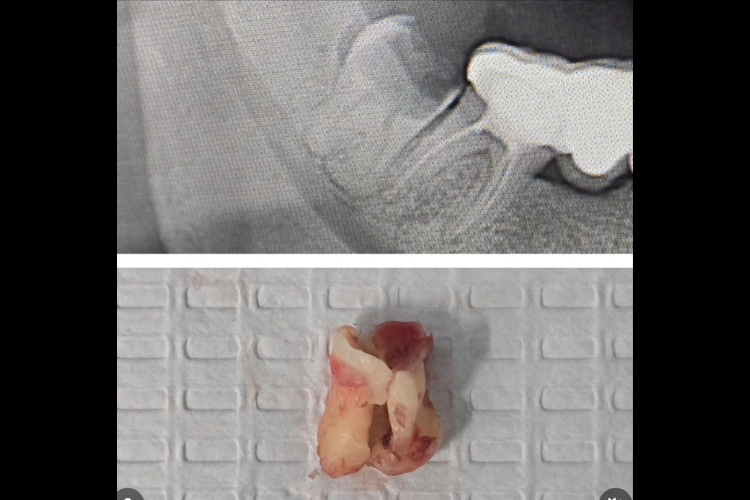

Impacted Carious Bulbous Wisdom Tooth Removal

Dr Raj removed this carious bulbous wisdom tooth. Our patient was suffering from severe pain from his grossly carious lower wisdom tooth. Lots of Dentists were unable to…